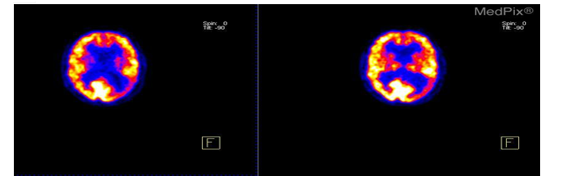

The objective of this experiment was to implement and evaluate a wavelet-based image compression and decompression system using Python libraries, specifically OpenCV and PyWavelets, on PET images shown in Figure 1. The initial step in setting up the required environment was installing the necessary Python libraries, which include Matplotlib and NumPy for numerical operations and visualization, respectively, and OpenCV for image handling and PyWavelets for wavelet transformations. The application was then loaded with the sliced images. To make things simple, OpenCV was used to read the photos in grayscale mode, which works well for intensity-based analysis. The grayscale image was first compressed by applying the Discrete Wavelet Transform (DWT), which divided the image into its wavelet coefficients. The image is represented by these coefficients at various resolution settings. The DWT was carried out using the PyWavelets module, and the Haar wavelet was chosen for this particular experiment.